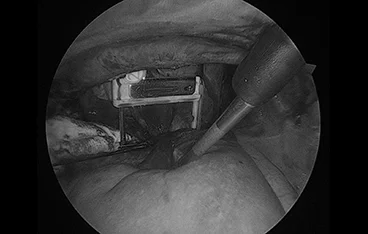

📍 폐엽절제

폐엽절제 전

폐엽절제 후

정확한 진단과 수술로 삶의 질을 회복합니다